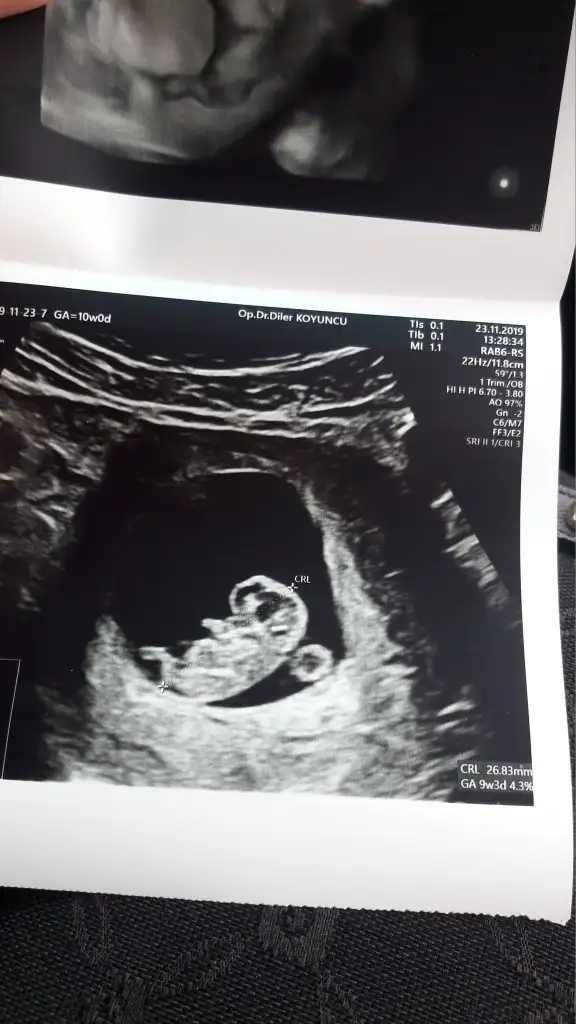

Boyle bi goruntusu var teyzeleri icimden kiz geciyor ama doktor bu goruntu kizda da boyle erkekte de boyle gorunur dedi 10 gun sonra bakalim tekrar cinsiyet icin dedi

Eklentiler

• 20191125_182309.webp

20191125_182309.webp

16,1 KB · Görüntüleme: 64